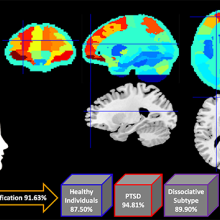

In a new study from Lawson Health Research Institute and Western University, researchers combined brain imaging and machine learning to classify with 92 per cent accuracy whether individuals had PTSD and whether or not it was the dissociative subtype. The results highlight the promise of brain imaging as a tool for early diagnosis of psychiatric illness, helping to predict symptom development and treatment needs.

Brain scans from Lawson research study

Brains scans and machine learning were combined to classify PTSD with 92 per cent accuracy.

In the second part of the study, the research team inputted the patterns of brain activity into a machine learning computer algorithm. They found the machine learning system could analyze brain scans to predict whether an individual had PTSD, the dissociative subtype of PTSD or no PTSD with 92 per cent accuracy.